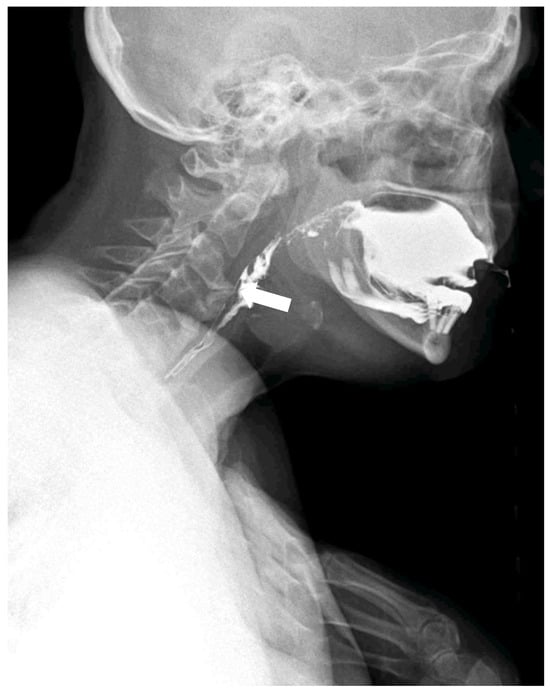

Figure 1. Static X-Ray acquisition acquired with Konica Minolta (AeroDR TX, Konica Minolta Inc., Tokyo, Japan) with a static setting. The cervical X-Ray shows florid, flowing ossification along the anterior or right aspects of five contiguous vertebrae, from C3 to C7 [,,,,,]. The intervertebral disk spaces are preserved.

Figure 2. Dynamic swallowing study (Konica Minolta, AeroDR TX, Konica Minolta Inc., Tokyo, Japan) during the administration of 30 mL barium and water in the laterolateral view. The distance between the tube and detector was set at 120 cm. Acquisition parameters: tube voltage, 60 kV; tube current, 80 mA; 15 fps, according to a previous study []; with acquisition time of 28 sec. The huge osteophyte of C3, associated with the coarse calcification of the anterior ligament, results in a narrowing of the pharyngeal lumen (arrow).